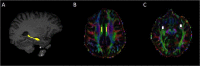

The clinical significance of anti-neuronal antibodies for psychiatric disorders is controversial. We investigated if a positive anti-neuronal antibody status at admission to acute psychiatric inpatient care was associated with a more severe neuropsychiatric phenotype and more frequent abnormalities during clinical work-up three years later. Patients admitted to acute psychiatric inpatient care who tested positive for N-methyl-D-aspartate receptor (NMDAR), contactin-associated protein 2 (CASPR2) and/or glutamic acid decarboxylase 65 (GAD65) antibodies (n = 24) were age - and sex matched with antibody-negative patients (1:2) from the same cohort (n = 48). All patients were invited to follow-up including psychometric testing (e.g. Symptom Checklist-90-Revised), serum and cerebrospinal fluid (CSF) sampling, EEG and 3 T brain MRI. Twelve antibody-positive (ab+) and 26 antibody-negative (ab-) patients consented to follow-up. Ab+ patients had more severe symptoms of depression (p = 0.03), psychoticism (p = 0.04) and agitation (p = 0.001) compared to ab- patients. There were no differences in CSF analysis (n = 6 ab+/12 ab-), EEG (n = 7 ab+/19 ab-) or brain MRI (n = 7 ab+/17 ab-) between the groups. In conclusion, anti-neuronal ab+ status during index admission was associated with more severe symptoms of depression, psychoticism and agitation at three-year follow-up. This supports the hypothesis that anti-neuronal antibodies may be of clinical significance in a subgroup of psychiatric patients.